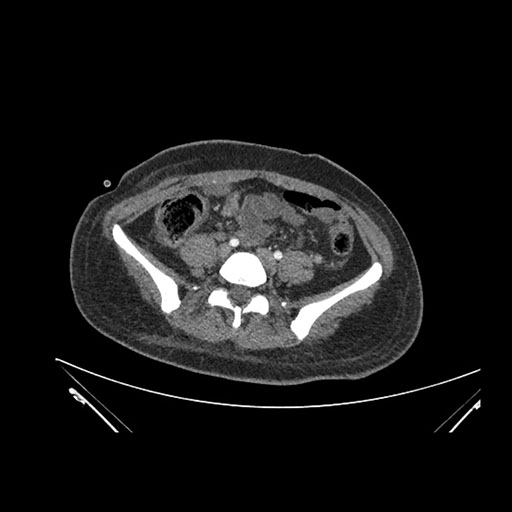

Imaging Analysis

Look through the patient's CT scan to identify any areas of concern for the necessary procedure.

Axial Arterial

Based on initial findings, which issue(s) would you be most concerned about?